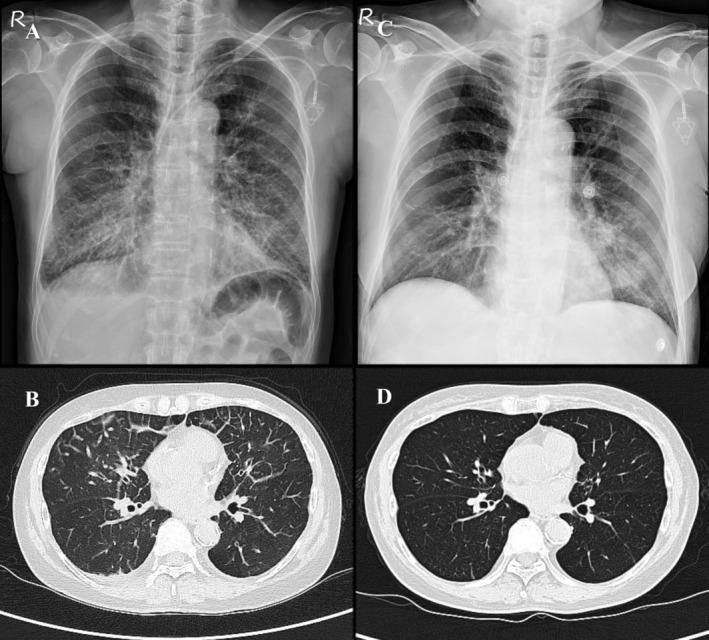

We describe a case of a 61-year-old woman with stage IV lung adenocarcinoma (cT4N0M1a) and contralateral lung metastases who developed immune-related adverse events (irAEs) following the 8th maintenance cycle of pembrolizumab and pemetrexed. Despite initiating systemic corticosteroids, her condition rapidly deteriorated into multiple organ dysfunction syndrome with elevated interleukin-6 (IL-6) levels. Tocilizumab was administered for suspected cytokine release syndrome (CRS) but resulted in minimal improvement. However, the subsequent administration of combined intravenous immunoglobulin (IVIG) and high-dose systemic corticosteroids led to gradual recovery, and she was ultimately discharged in a stable condition.